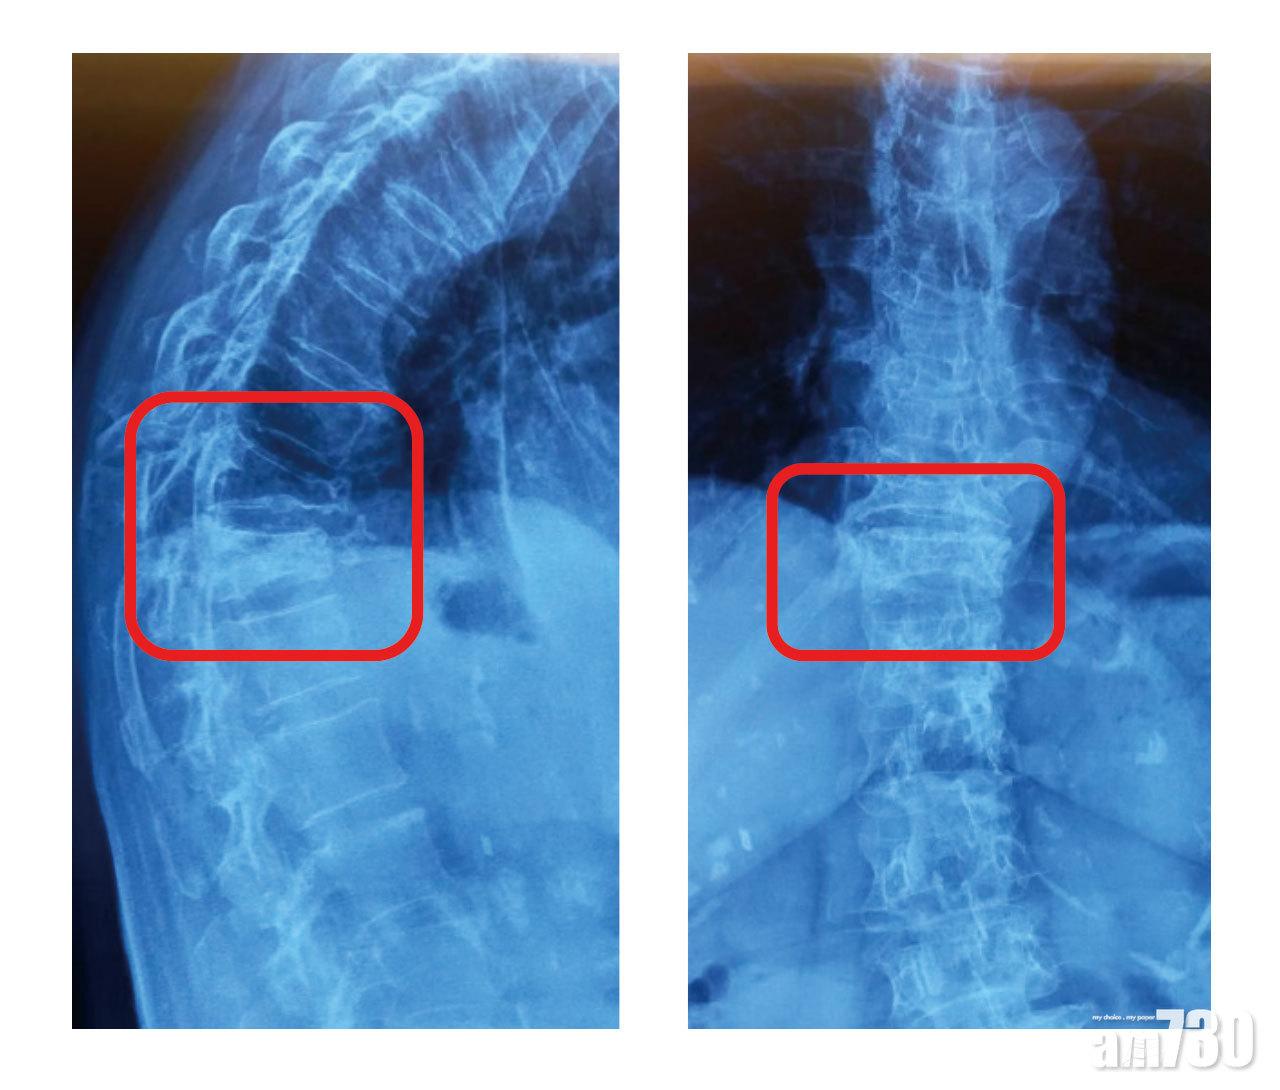

胸椎骨折

現年88歲的葉婆婆,性格外向,平日會返教會、到老人中心唱粵曲,甚至外遊。數月前因為胸口及背痛入院,起初以為是心臟問題,及後檢測骨質密度,才發現脊椎密度大部分T值低於-2.8,屬嚴重骨質疏鬆,而且胸椎有骨折。確診後,醫生處方仿保骨素針、鈣片及維他命D補充劑,幸而骨折對生活沒大影響。此外,女兒劉小姐骨質密度也處於骨質疏鬆邊緣,現也會多曬太陽及做運動,減少骨折風險。